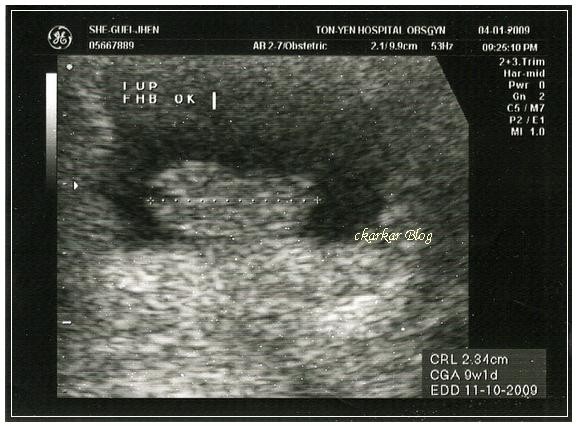

這是4/1產檢時的超音波照片,9w1d、2.34cm 已經有心跳,在醫院等待的時間很長,最後的結果很令人開心!!